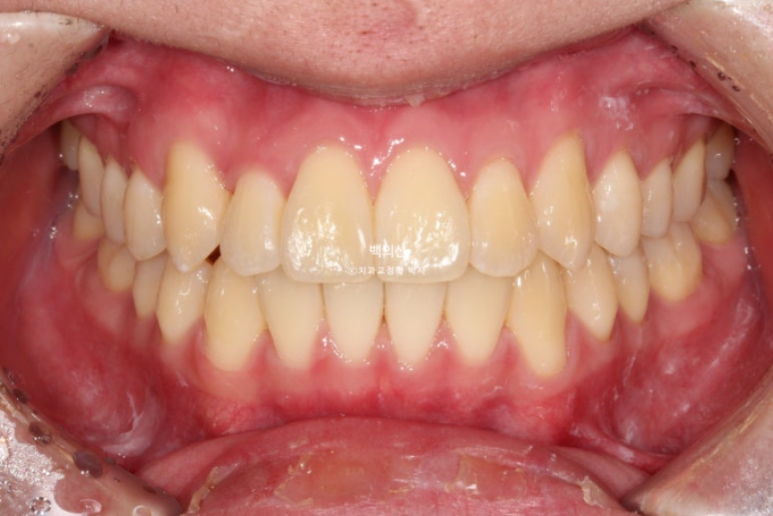

24.12

덧니와 반대교합은 해소가 되었습니다.

교합은 좋고 양쪽 다 1급 교합관계를 보입니다.

배열도 완벽 합니다.